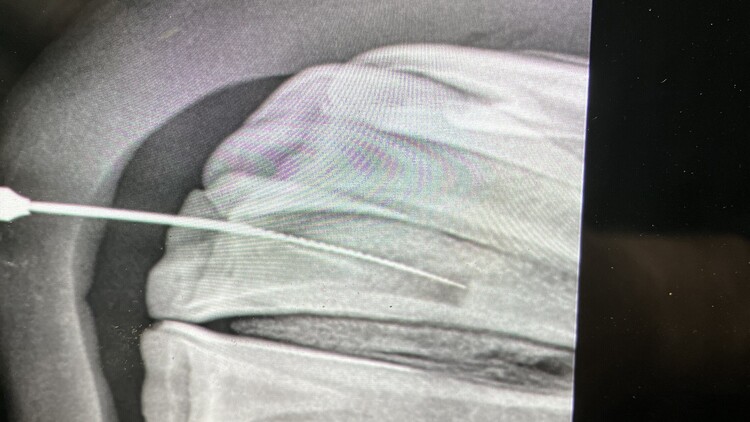

Tooth Extraction

We specialise in equine dentistry and that is all we do. Therefore each year we carry out hundreds of advanced equine dentistry procedures. These range in severity from fillings, to simple extractions to sinus surgery.